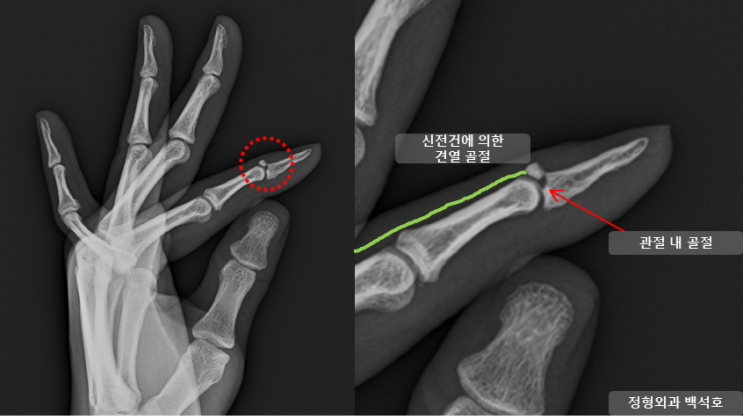

[골성 망치 수지] 농구공에 맞은 뒤 손가락이 부었어요. ; 골성 추지, 손가락 견열 골절, bony mallet finger

안녕하세요 중랑구 골절 수술 전문의 마디세상 병원 백석호 원장입니다. 병력 농구 시합 중 농구공에 손가...